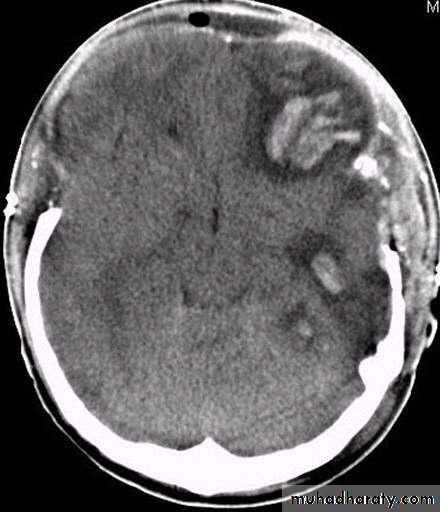

3. Brainstem and hemispheric (Cerebral) Contusion

These are areas of bruising and swellings with intact pia arachnoid, localized or generalized oedema and haemorrhage due to tearing of blood vessels.

3. Cerebral Contusion

Clinical presentations:

1. Prolonged periods of unconsciousness.

2. Focal neurological deficits that persist for longer than 24 hours.

CT scans demonstrates contusions as small areas of haemorrhage in the cerebral parenchyma.

Contusions may resolve with the accompanying deficits or they may persist.